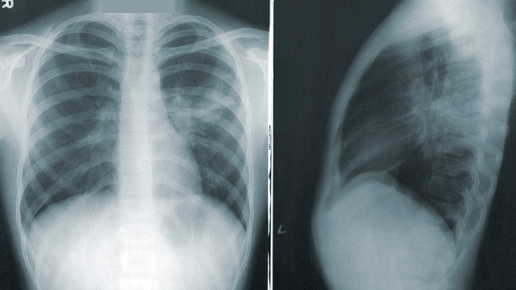

Пневмония — это группа острых респираторных инфекционно-воспалительных заболеваний нижних дыхательных путей. Заболевание характеризуется очаговым поражением легочной ткани. При пневмонии альвеолы легких заполняются жидкостью (экссудатом), что приводит к нарушению дыхания и газообмена, а в дальнейшем — одышке и снижению сатурации кислорода крови. Пневмония относится к числу наиболее распространенных инфекционных заболеваний, занимает четвертое место среди причин смертности населения. Мировая статистика...

О том, почему возникает пневмония, как она лечится, и возможно ли предотвратить развитие этого заболевания, рассказала врач-пульмонолог, терапевт Юлия Михайловна Закиева. Причины и факторы риска развития пневмонии Пневмония — это группа острых инфекционных заболеваний, характеризующихся поражением альвеол и ткани легких. Пневмонию могут вызывать вирусы, бактерии и грибки. Факторы риска развития пневмонии: Методы лечения пневмонии 1. Антимикробная терапия: Препараты подбираются строго в зависимости...

Пневмония не всегда быстро и правильно диагностируется. Именно из-за этого велик риск осложнений и даже летального исхода. Врачи настоятельно рекомендуют обращаться за профессиональной помощью при первых признаках заболевания. Ежегодно 12 ноября отмечается Всемирный день борьбы с пневмонией. Это воспаление легких, вызванное бактериями, вирусами или грибками. Заболевание может появиться как самостоятельное, но зачастую оно становится осложнением других болезней, например гриппа, коронавируса, СПИДа, опухолей легких, бронхоэктаза...